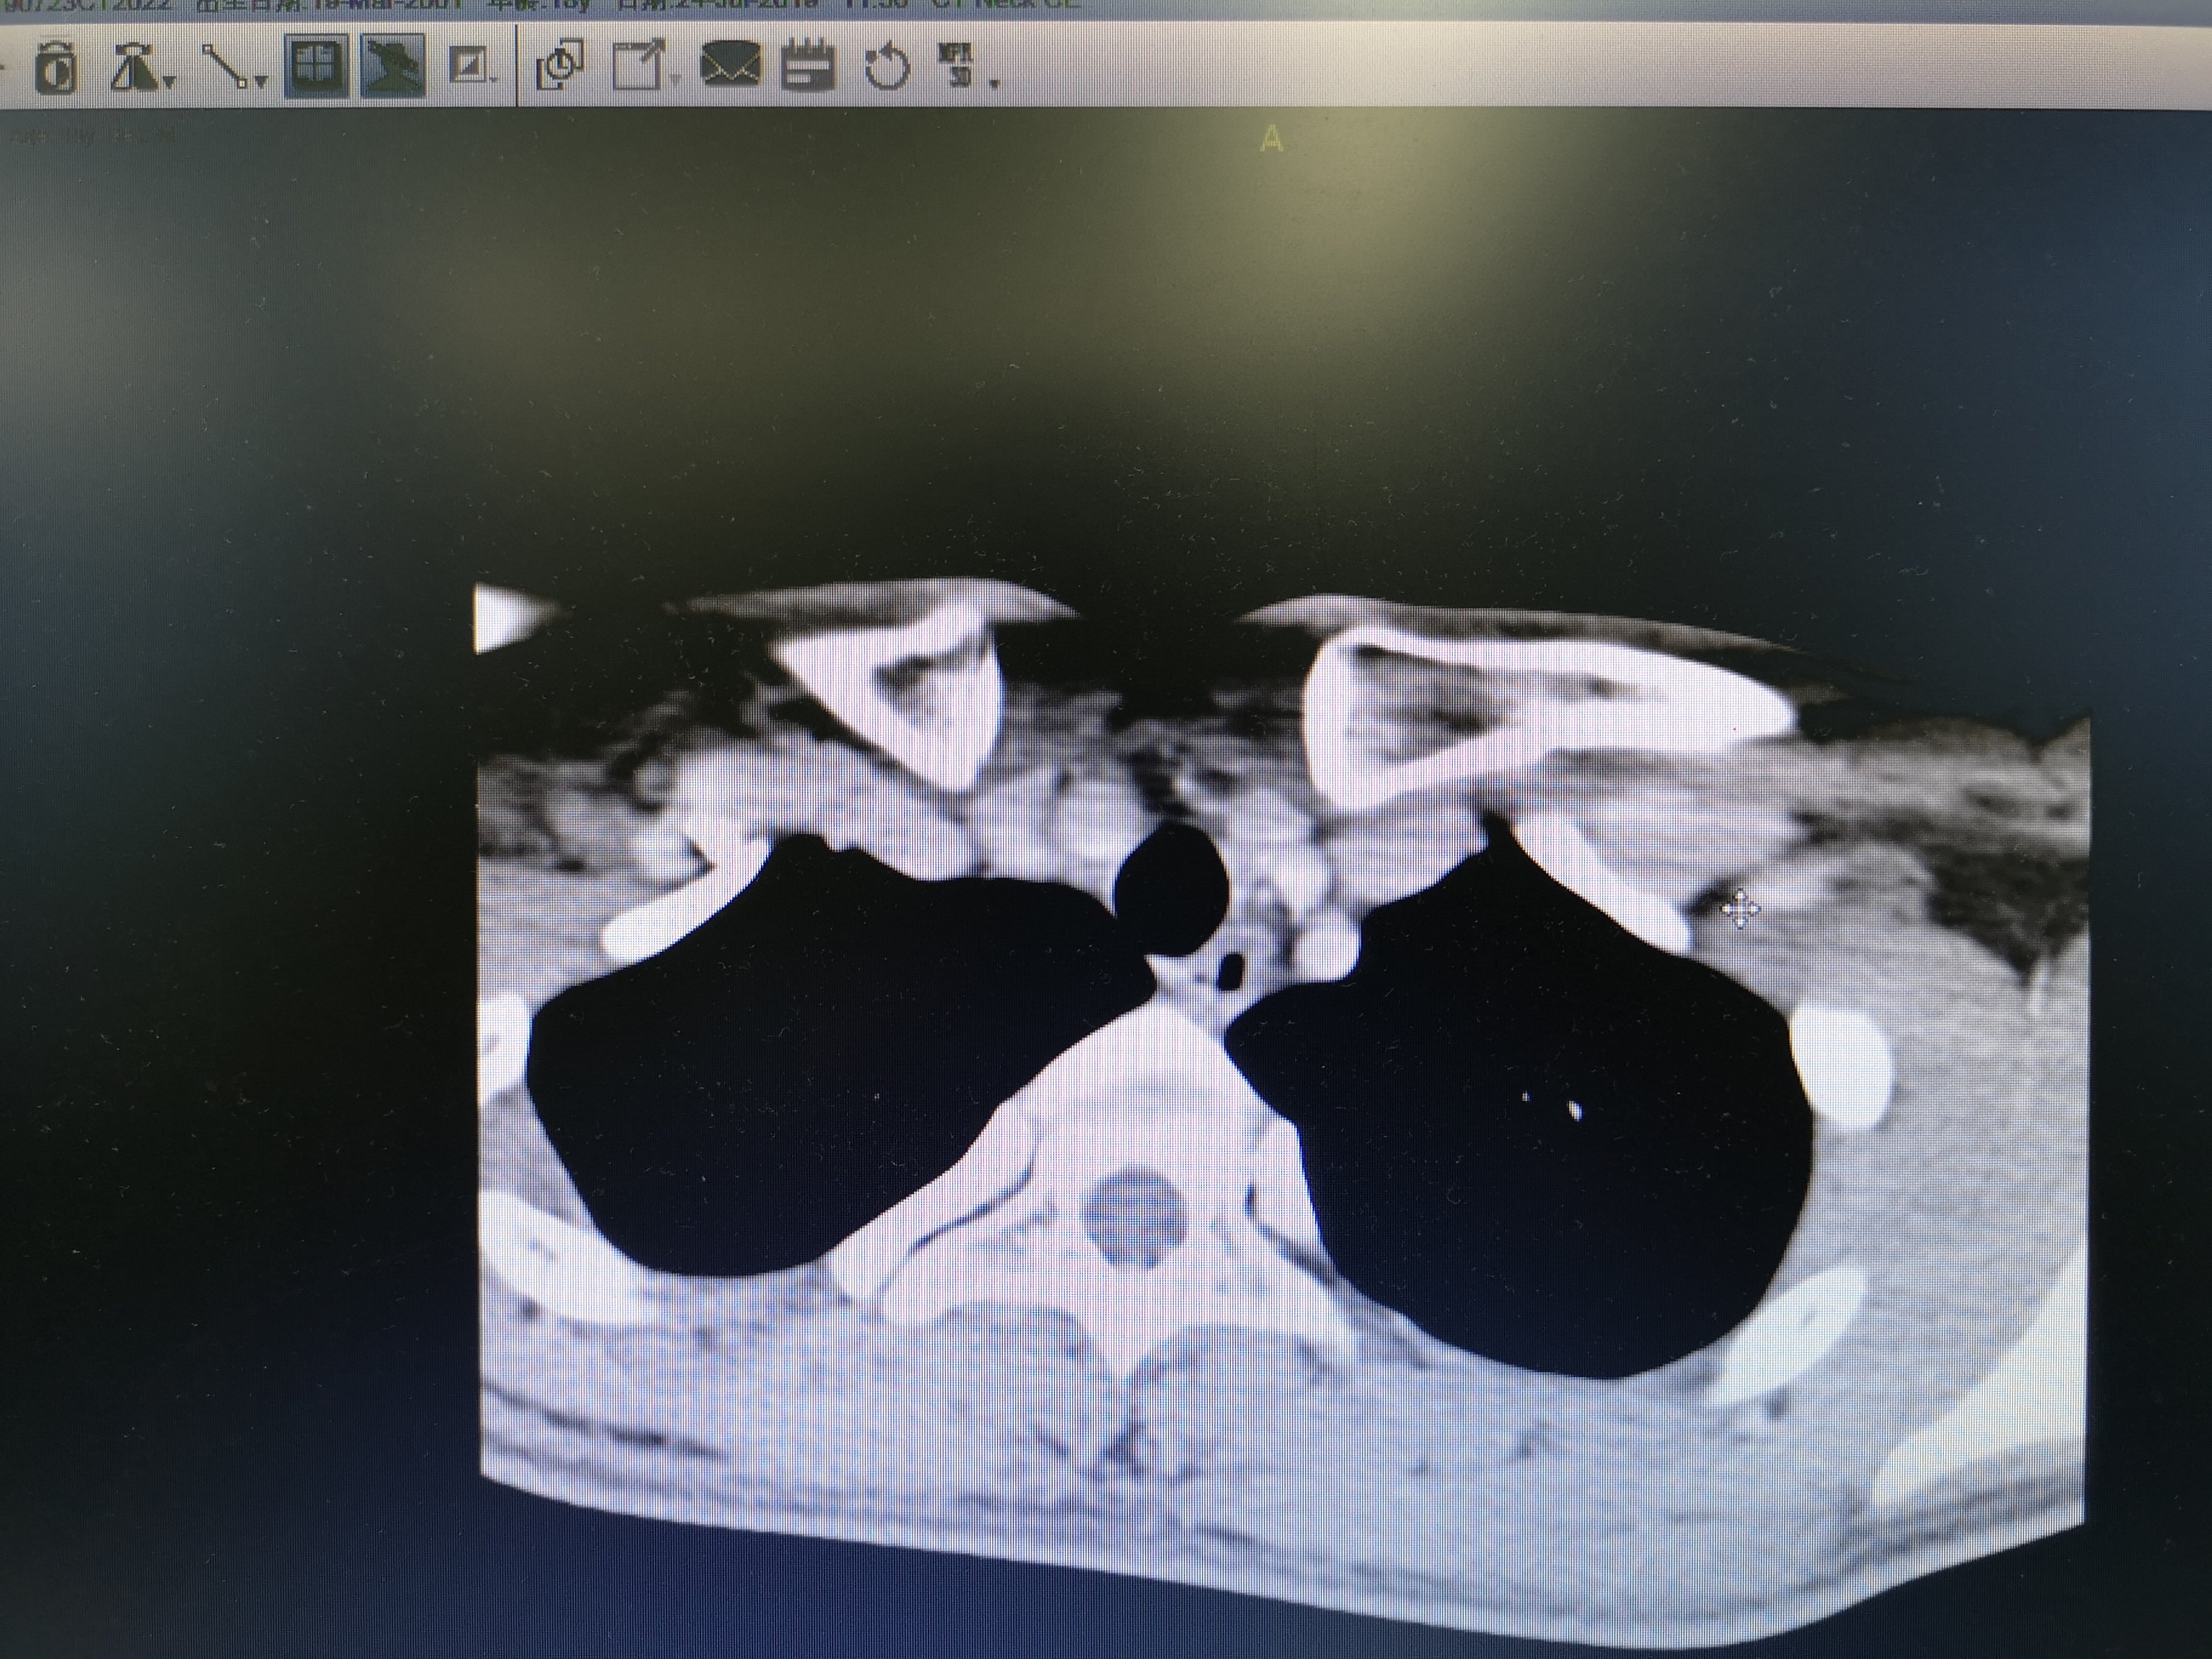

病例2 右2,右4R区,左6区残留,颈部切口清扫,未开胸